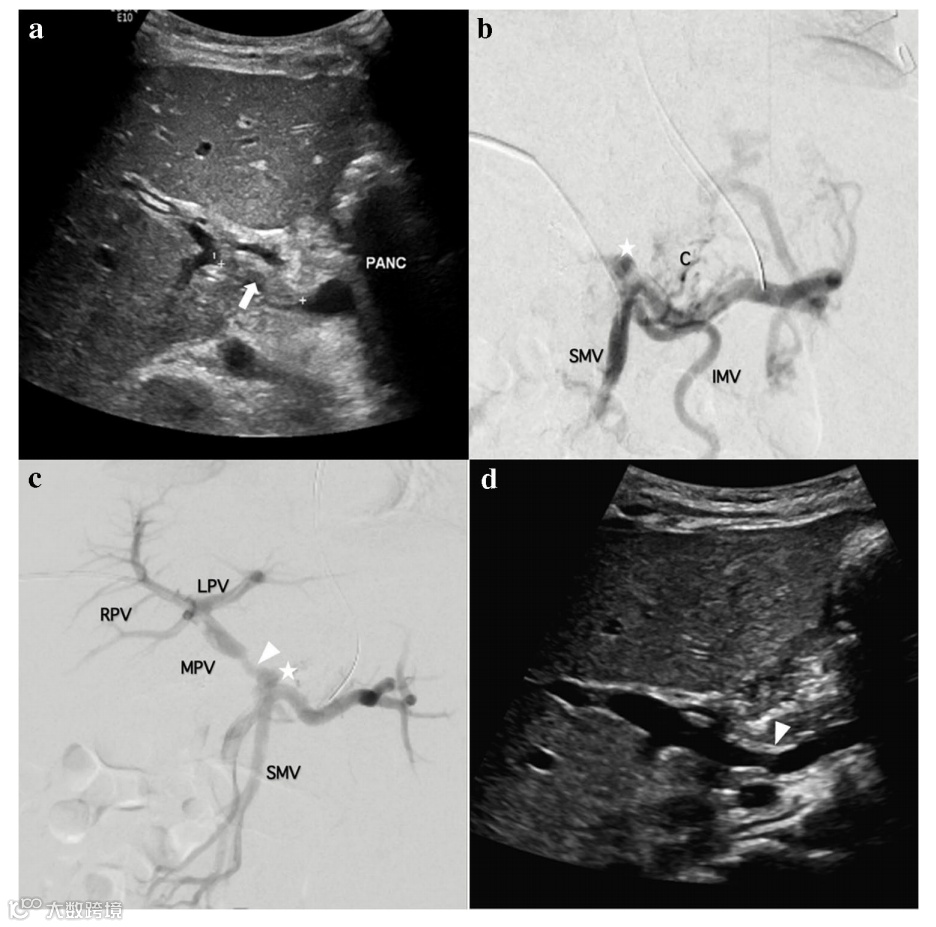

一名九个月大的患儿(8.4 kg)胆道闭锁接受原位肝移植后出现PVT。

图a:介入前,超声显示门静脉内有急性血栓形成(白色箭头)。胰腺头部标记为“PANC”。

图b:介入前,静脉造影显示门静脉闭塞(白星)。

图c:介入后,静脉造影显示门静脉肝内分支血流重新恢复,表明溶栓治疗成功。

图d:介入后,超声显示门静脉再通和血栓切除术后残余狭窄部位(箭头)。